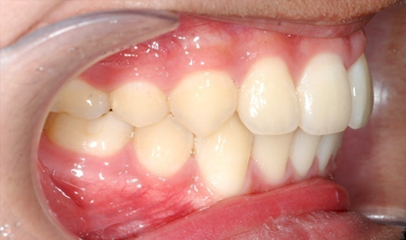

발치 돌출입 교정

전후 사례

발치 교정, 치료기간 약 2년

After